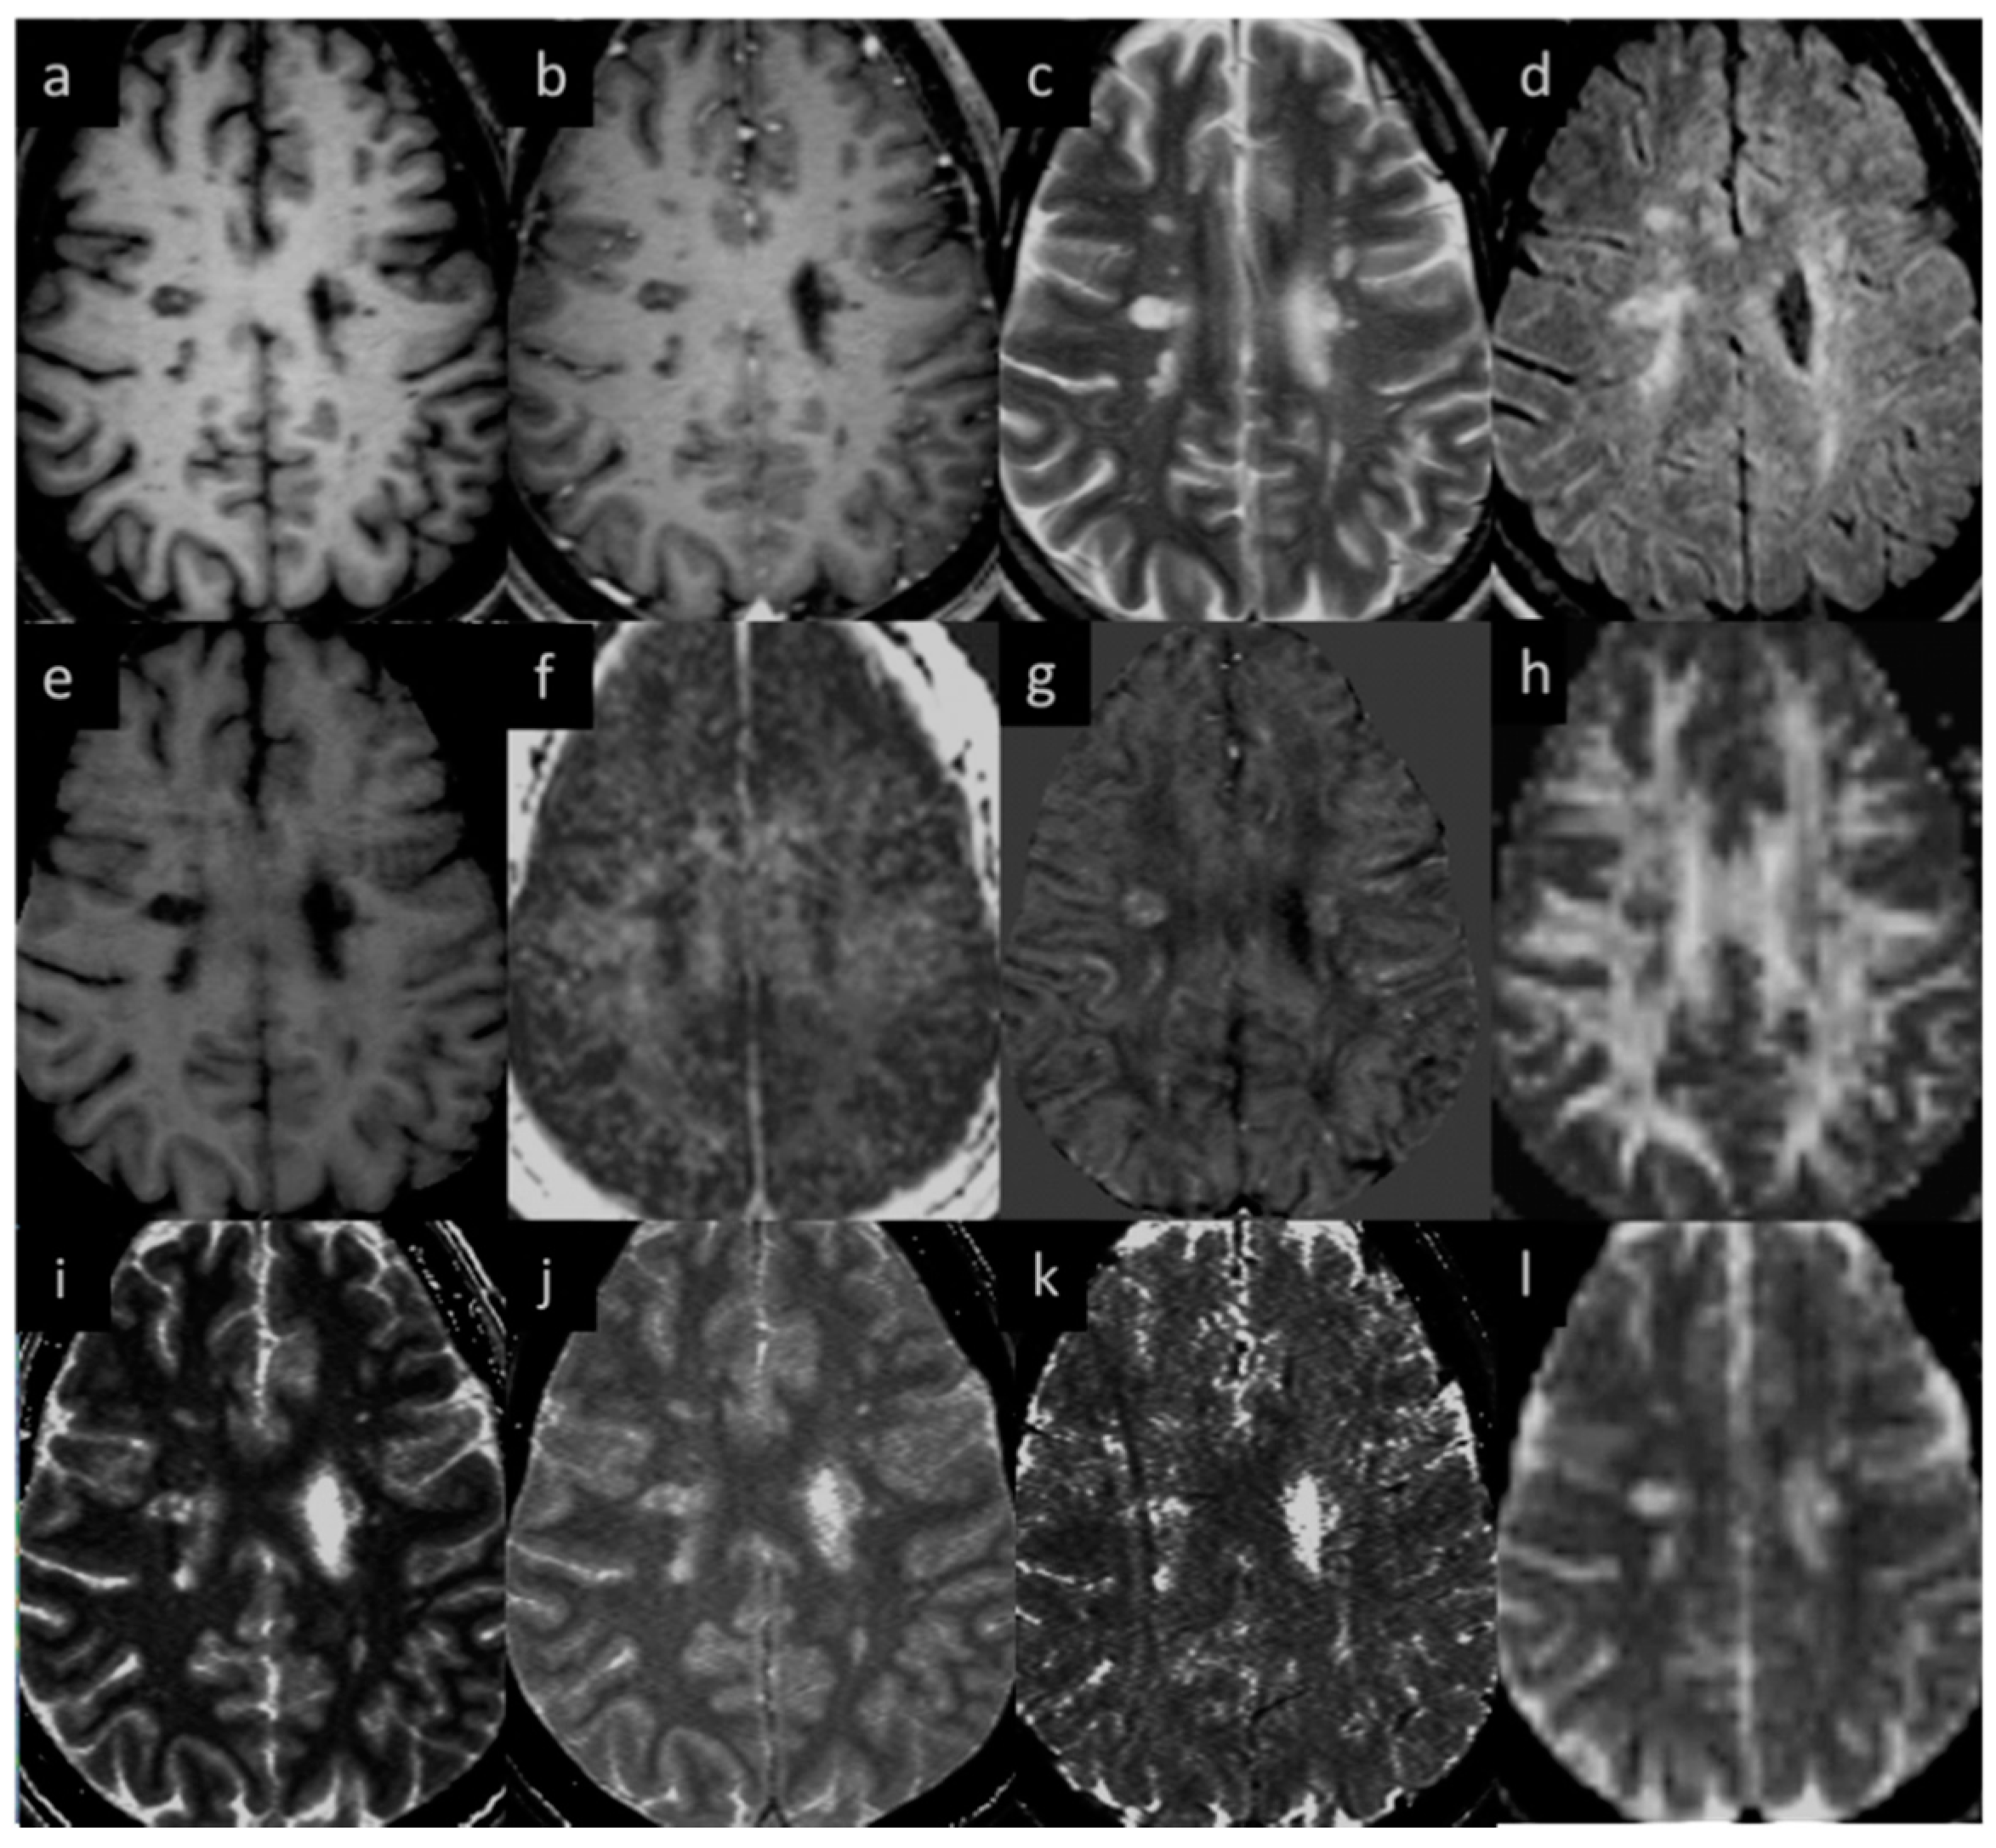

Eighteen (out of twenty) MS subjects had lesions at both time points. An example image of a typical MS lesion appearance across all modalities and their image quality is shown in Figure 2. Two of the MS subjects had no visible lesions in T2 FLAIR. The remaining eighteen MS subjects had visible deep and periventricular WMHs in T2 FLAIR. The lesion count in MS subjects varied from 2 to 84 lesions in the 18 subjects. Six subjects had lesion loads between 0.1 and 1.0 cc, eight subjects had lesion loads between 1.0 and 10 cc, and four MS subjects had diffuse WMH volume that exceeded 25 cc as measured from the T2 FLAIR data. The overall lesion burden did not change between time points in the six-month period between scans for any of the subjects.

Figure 2.

Lesion appearance in different modalities: (a) pre-contrast T1W, (b) post-contrast T1W, (c) T2WI, (d) T2 FLAIR, (e) MTR, (f) MWF, (g) QSM, (h) FA, (i) T1MAP, (j) PSDMAP, (k) T2STAR, and (l) ADC.

MWF had a thicker slice than other modalities and lower resolution, making it difficult to see smaller lesions; however, larger lesions could still be easily visualized. In total, 162 of 384 (42.2%) QSM-positive lesions and 29 of 94 (30.8%) QSM-negative lesions were visible in the MWF images. An example image showing MWF compared to other modalities is shown in Figure 7. The MWF correlated with susceptibility for QSM visible lesions, indicating that both methods were sensitive to loss of myelin fibers in white matter lesions (see Figure 8, p-value = 0.01). It can be seen from Figure 2 and Figure 7 that lesion appearance differs between modalities. FLAIR lesions are diffuse, lesions in modalities such as T1, T2WI, MTR are smaller and QSM lesions are local and have different volumes.

Both T2 FLAIR and T2W imaging showed the most lesions and the clearest lesions out of all methods, while DTI measures showed lesions the worst because of their low resolution and poorer contrast-to-noise ratio. The reason all the DTI measures correlated with each other is likely to have been the presence of chronic lesions with high water content. Although DTI can be sensitive to some pathological mechanisms, the presence or absence of lesions is not dependent on DTI data. Similarly, the increases in water content (as shown in the proton spin density weighted imaging data) in chronic lesions leads to an increase in the signal from the T2 component. Generally, water content should be considered when measuring MWF changes in acute lesions [33], and it is also believed that the change in total water content could cause the decrease in MWF that was observed after iron extraction [3]. Further, it has been shown that a change in MWF does not necessarily reflect a change in myelin content and that the sensitivity of myelin water fraction to changes in iron content in the brain has far reaching consequences [34].